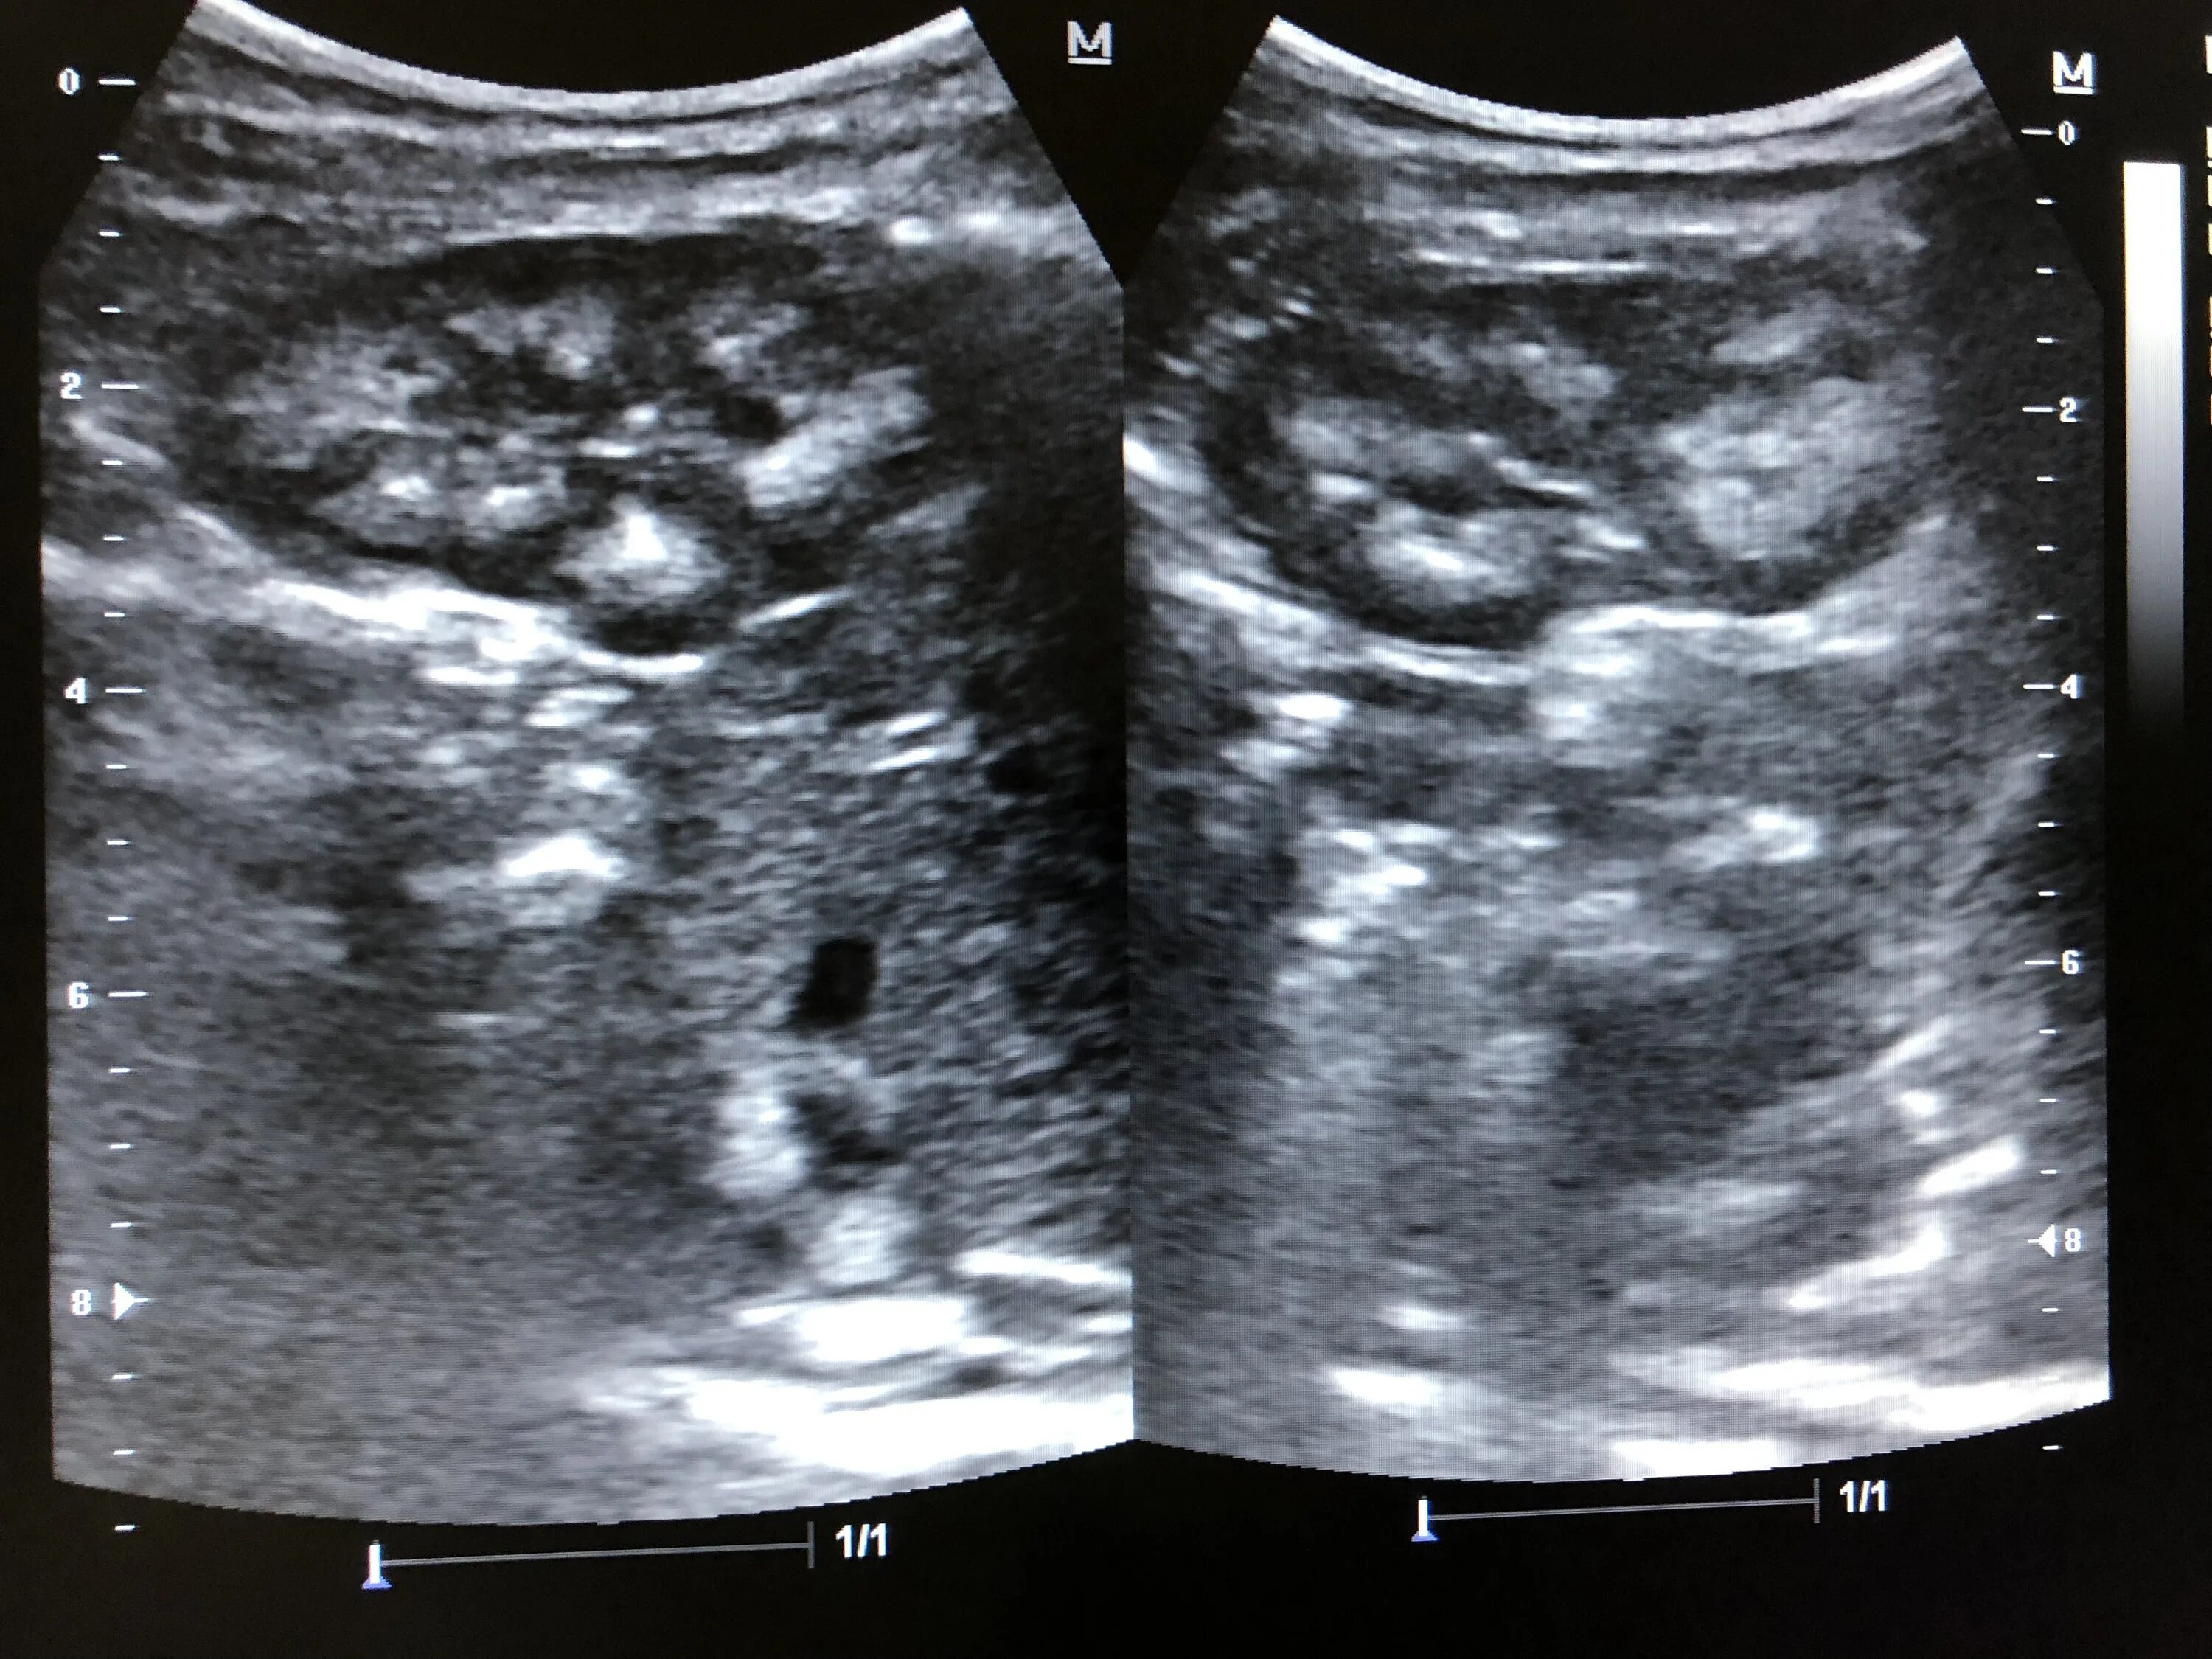

Гиперэхогенные пирамиды в почках на узи. синдром гиперэхогенных пирамидок на узи. медуллярный нефрокальциноз почек узи. медуллярная губчатая почка узи.

Синдром гиперэхогенных пирамид на узи. синдром гиперэхогенных пирамид почек узи. медуллярная губчатая почка узи. гиперэхогенные пирамидки в почках на узи.

Медуллярная кистозная дисплазия почек узи. гиперэхогенные пирамиды на узи. гиперэхогенные пирамиды в почках на узи. кортико-медуллярная дифференциация выражена узи почек.

Симптом выделяющихся пирамид на узи. синдром гиперэхогенных пирамид на узи. синдром гиперэхогенных пирамид почек узи. медуллярная губчатая почка узи.

Нефрокальциноз почек на узи. синдром гиперэхогенных пирамид почек узи. медуллярная губчатая почка узи. гиперэхогенные пирамидки в почках на узи.

Синдром гиперэхогенных пирамид почек узи. микролиты в почках на узи. синдром гиперэхогенных пирамидок на узи. утолщение паренхимы почек на узи.

Синдром выделяющихся пирамид. гиперэхогенные пирамидки. симптом гиперэхогенных пирамидок. синдром гиперэхогенных пирамид почек.

Гиперэхогенные пирамидки в почках на узи. синдром гиперэхогенных пирамидок почек. синдром гиперэхогенных пирамид почек узи. медуллярная кистозная дисплазия почек узи.

Гиперэхогенные пирамиды в почках на узи. синдром гиперэхогенных пирамидок почек на узи. синдром гиперэхогенных пирамид на узи. узи признаки гиперэхогенных пирамидок.

Гиперэхогенные пирамидки в почках на узи. симптом выделяющихся пирамид на узи. узи признаки гиперэхогенных пирамидок. синдром гиперэхогенных пирамид почек узи.

Синдром гиперэхогенных пирамид почек узи. медуллярный нефрокальциноз почек узи. губчатая почка узи картина. гиперэхогенные пирамидки в почках на узи.